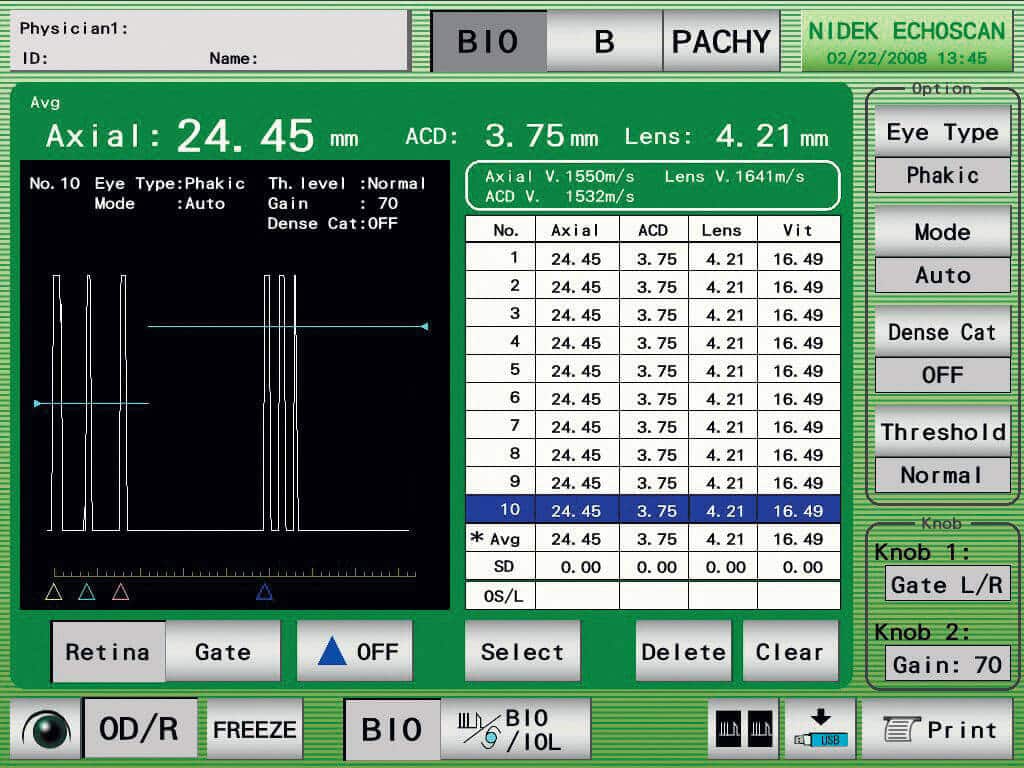

Nidek US-4000

Ultraschall A/B Scan mit Pachymtrie

Kompaktes, modular ausbaubares Instrument. Durch das kontrastreiche Display können B-Scan sehr gut auf dem Display live angesehen werden. Verschiedene Bearbeitungsprogramme lassen eine perfekte Lokalisation zu. Sehr einfache Bedienung durch den Touch Scren Bildschirm, schnelles abspeichern von Messungen, Druckmöglichkeit durch den integrierten Printer oder USB Interface für Datenexport. Zur Kalkulation von IOL und Patientenverwaltung. IOL Formula (SRK, SRK2, SRK-T, Binkhorst, Holladay